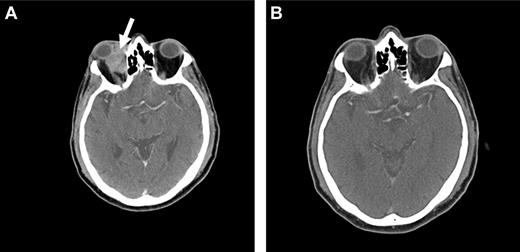

Because OAML is highly sensitive to radiotherapy, it is probable that radioimmunotherapy may be effective in controlling local disease as well as preventing distant relapse. At our institution, we are currently conducting a prospective phase 2 study using Y-90 ibritumomab tiuxetan (Zevalin) as first-line therapy in patients with newly diagnosed marginal zone lymphoma of all sites. Initial data suggest that this agent may be highly active and a useful approach in the treatment of OAML, with a favorable side effect profile (Figure 4).

Radioimmunotherapy with Y-90 ibritumomab tiuxetan (Zevalin). Pretreatment (A) and posttreatment (B) CT imaging of a patient with OAML involving the right orbit (arrow), demonstrating a complete response 12 weeks after radioimmunotherapy.